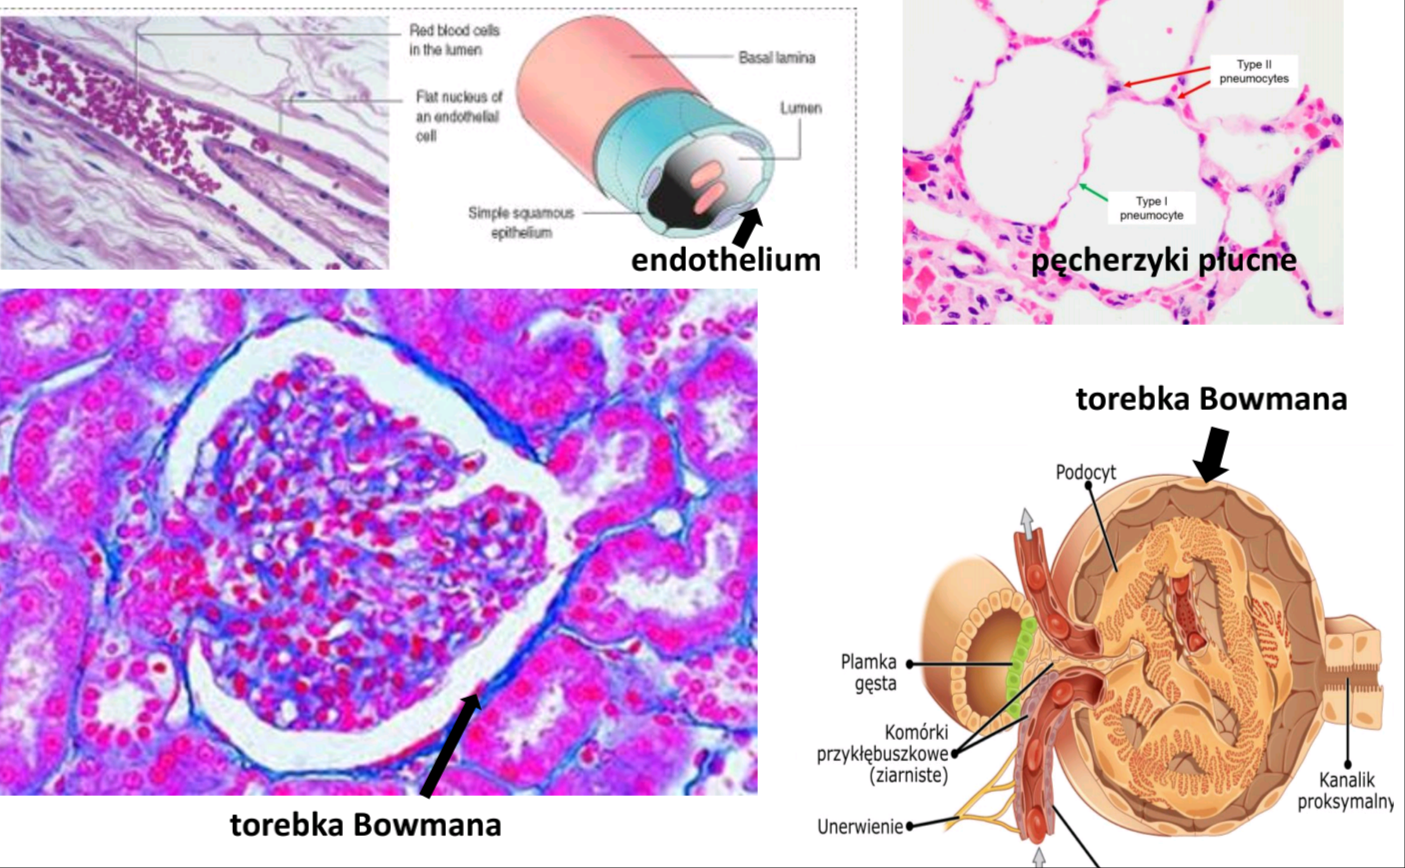

Nabłonek jednowarstwowy płaski

Gdzie?- śródbłonek (=endotelium), międzybłonek (=mezotelium), torebka Bowmana, pęcherzyki płucne, nabłonek opłucowy, sercowy

Co to jest śródbłonek (endotelium)?

To nabłonek wyścielający naczynia krwionośne, limfatyczne, a także przedsionki i komory serca